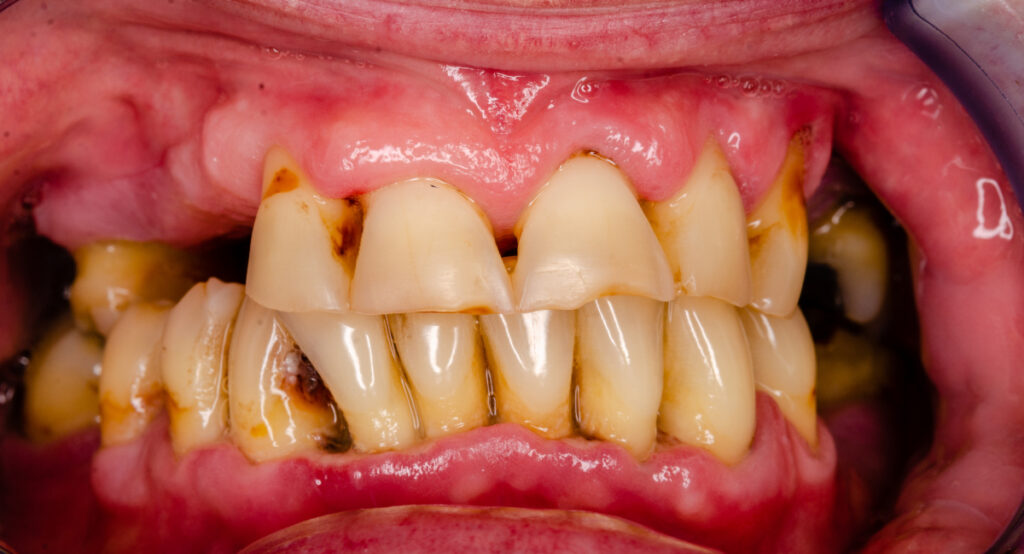

重度の歯周病の歯

歯周病は、初期段階では自覚症状がほとんどないまま進行することが多い病気です。いつの間にか進んでいる場合が多く、気づいたときには重度まで進行しているケースも少なくありません。重度まで進行すると、歯を支える骨が大きく失われ、最悪の場合、歯が抜け落ちるリスクが高まります。

歯周病とは、歯を支えている歯槽骨や歯ぐきなどの歯周組織に炎症が生じる病気です。初期段階では歯肉炎と呼ばれ、歯ぐきに軽い炎症が起こります。やがて炎症が深部に進むと歯周炎へと進行して歯を支える骨が破壊されていき、最終的に歯を失うこともあります。

重度の歯周病の主な症状

重度の歯周病になると、以下のような症状が現れることがあります。思い当たることがある方は、早めに歯科医師に相談しましょう。